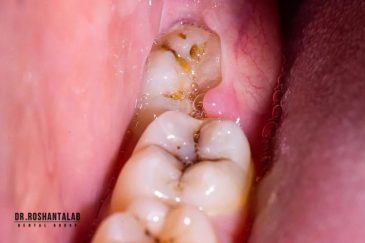

از عصب کشی و درمان ریشه دندان گرفته تا جراحی لثه و کشیدن دندان، تمامی مراحل توسط متخصص ترمیم دندان مدیریت میشود. ارائه باکیفیتترین خدمات ترمیم دندان برای سلامتی شماست.کاشت ایمپلنت فوری دندان